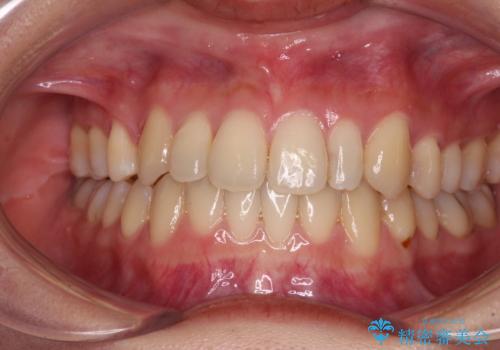

遠方から新幹線で通院 急速拡大装置とインビザラインによる矯正治療

- 小児矯正の頃から診察を行っている患者様です。

上顎骨の幅が下顎骨よりも小さいので、拡大装置により骨幅を広げて上下関係を改善し、その後インビザラインにて歯並びを整えることとしました。

上下の骨幅を改善したことで、スムーズに歯列矯正を行うことができました。

インビザライン治療開始直後に遠方に引っ越しをされたため、通院間隔が長くなり、治療期間が長くなりましたが、しっかりと治療を行うことができました。